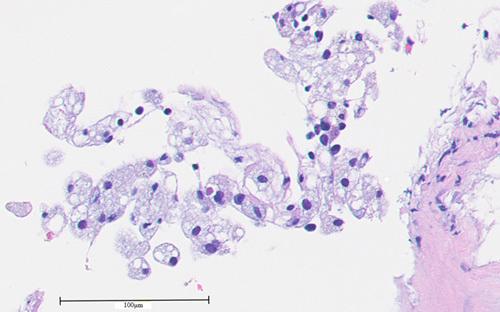

Xanthomatous Pleuritis Associated With Pancreaticopleural Fistula.

J Bronchology Interv Pulmonol. 2022 Apr 1;29(2):155-157. doi: 10.1097/LBR.0000000000000834.

Xanthomatous Pleuritis Associated With Pancreaticopleural Fistula.与胰胸膜瘘相关的黄色瘤性胸膜炎